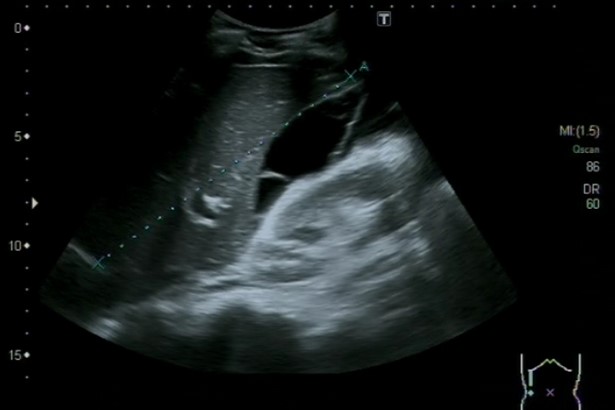

Ecografía abdominal, en la que se identifica abundante cantidad de líquido libre intraperitoneal, a nivel perihepático, periesplénico e interasas, sugestivo de asticis. Hígado, bazo, vía biliar, riñones y vejiga normales.

La ecografía clínica es una herramienta esencial en el diagnóstico de la ascitis. Permite la identificación y cuantificación precisa del líquido, además de evaluar su distribución. La realización de paracentesis guiada por ecografía es fundamental para establecer la causa subyacente de la ascitis, permitiendo obtener muestras de líquido para su análisis. La combinación de la ecografía y la paracentesis mejora la precisión diagnóstica y guía la atención médica apropiada.